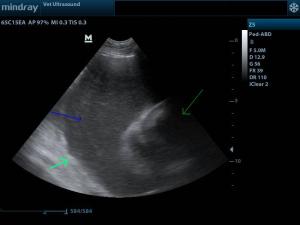

Αυτό μας καθοδήγησε πως πιθανόν ο ασκίτης να οφείλεται σε ανεπάρκεια της τριγλώχινης βαλβίδας της δεξιάς καρδιάς. Στον έλεγχο της καρδιάς διαγνώστηκε περικαρδιακή συλλογή με καρδιακό επιπωματισμό, και μία μάζα η οποία εντοπιζόταν στον δεξιό κόλπο.

(πράσινο βέλος περικάρδιο, μπλέ βέλος περικαρδιακή συλλογή)

Έγινε περικαρδιοκέντηση ο ασθενής ανακουφίστηκε άμεσα. Λόγω οικονομικών δυσκολιών ο ιδιοκτήτης δεν θέλησε να σταλεί για κυτταρολογικό έλεγχο το υγρό της περικαρδιακής συλλογής, εφόσον η πρόγνωση ήταν δυσμενής. Η συνήθης διαφορική διάγνωση για τα νεοπλάσματα της βάσης της καρδιάς είναι το χημειοδέκτωμα, το αιμαγγειοσάρκωμα το μεταστατικό νεόπλασμα του θυρεοειδή και άλλα σαρκώματα.